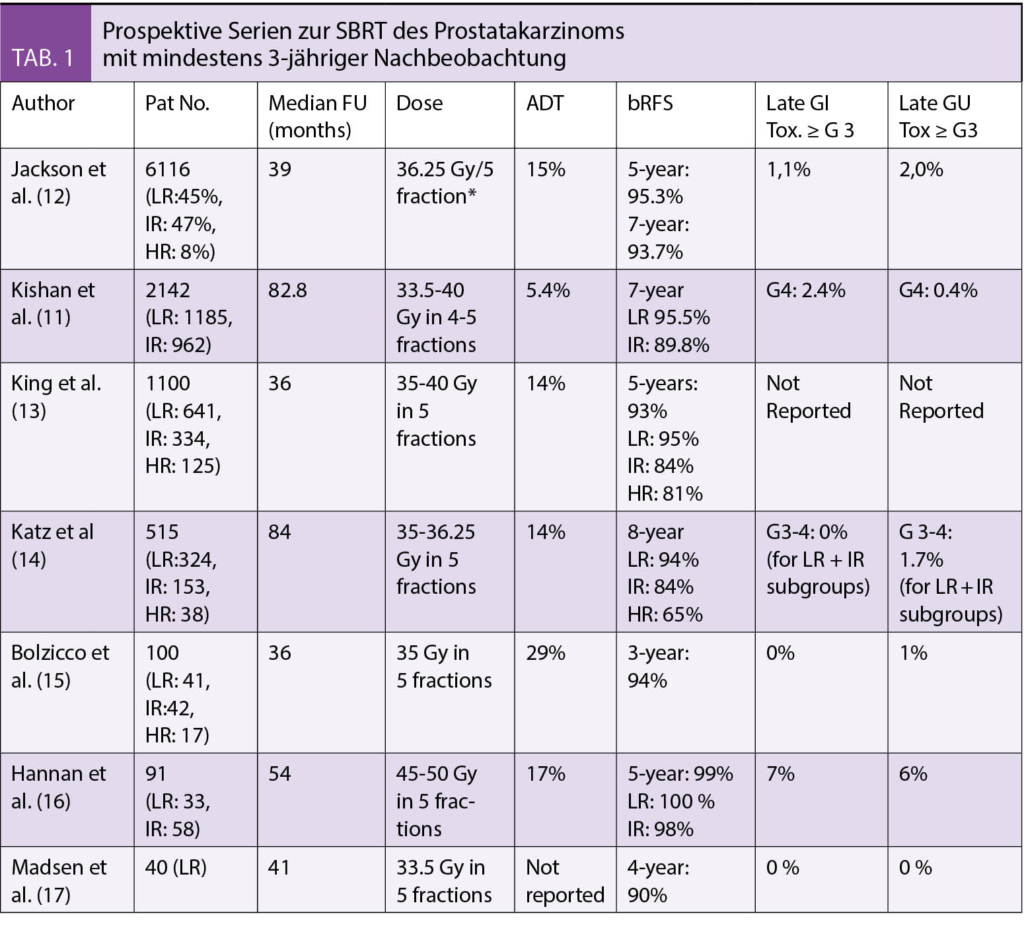

Es gibt mehrere veröffentlichte Serien, die den Einsatz von SBRT untersuchen (Tab. 1). Die grösste Analyse ist eine Kohortenstudie, die individuelle Patientendaten aus 12 Phase-II-Studien analysierte, die 2142 Männer mit low risk (LR) und intermediate rsik (IR) Prostatakrebs umfassten, die entweder mit CyberKnife oder einem konventionellen Linearbeschleuniger behandelt wurden. Ca. 55,3% der Patienten hatten eine LR Erkrankung, 32,3% eine favourable IR-Erkrankung und 12,4% eine unfavourable IR-Erkrankung. High risk (HR)-Patienten wurden ausgeschlossen. Die Nachbeobachtungszeit betrug 6,9 Jahre (Median) (11). Das siebenjährige biochemische freie Überleben (bRFS) betrug 95,5% für die LR-Krankheit, 93.7% bei favourable IR und 86.5% bei unfavorable IR Patienten. Die Inzidenz von akuten toxischen Ereignissen Grad 3 oder höher betrug 0,60% für urogenitale (GU) und 0,09% für gastrointestinal (GI) Toxizitäten.

Die neueste Metaanalyse wurde von Jackson et al. durchgeführt, die 6116 Patienten aus 38 prospektiven Studien umfasste (12). Hier wurden nur Studien gepoolt, die zum gleichen Zeitpunkt den gleichen Endpunkt berichteten, was eine inhärente Einschränkung darstellt. Auf Patientenebene hatten 45% eine LR-, 47% eine IR- und 8% eine HR-Erkrankung. Die mittlere Nachbeobachtungszeit betrug 39 Monate, was bei der Bewertung der 5- und 7-Jahres bRFS-Raten und Toxizitäten berücksichtigt werden muss. Die kombinierte akute ≥ G3 Toxizität lag unter 1%. Die späte ≥ G3 GU- und GI-Toxizität betrug 2,0% bzw. 1,1% und änderte sich nicht, wenn nur Studien mit einer medianen FU von ≥5yr ausgewertet wurden. Interessanterweise gab es einen Zusammenhang zwischen Dosis und ≥ G3 GU-Toxizität, aber nicht mit ≥ G3 GI-Toxizität. Die Autoren kommen zu dem Schluss, dass die Ultra-Hypofraktionierung als strahlentherapeutische Standardstrategie für lokalisiertes Prostatakarzinom angesehen werden könnte – eine Aussage, die zwar für LR- und IR-Patienten ernstgenommen werden muss, aber für unterrepräsentierte HR-Patienten noch nicht validiert ist.